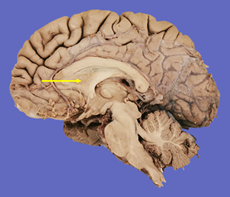

Q9. Marked structure separates which of the following:

- Third ventricle

- Lateral ventricle

- Fourth ventricle

- Cisterna magna

Answer – B